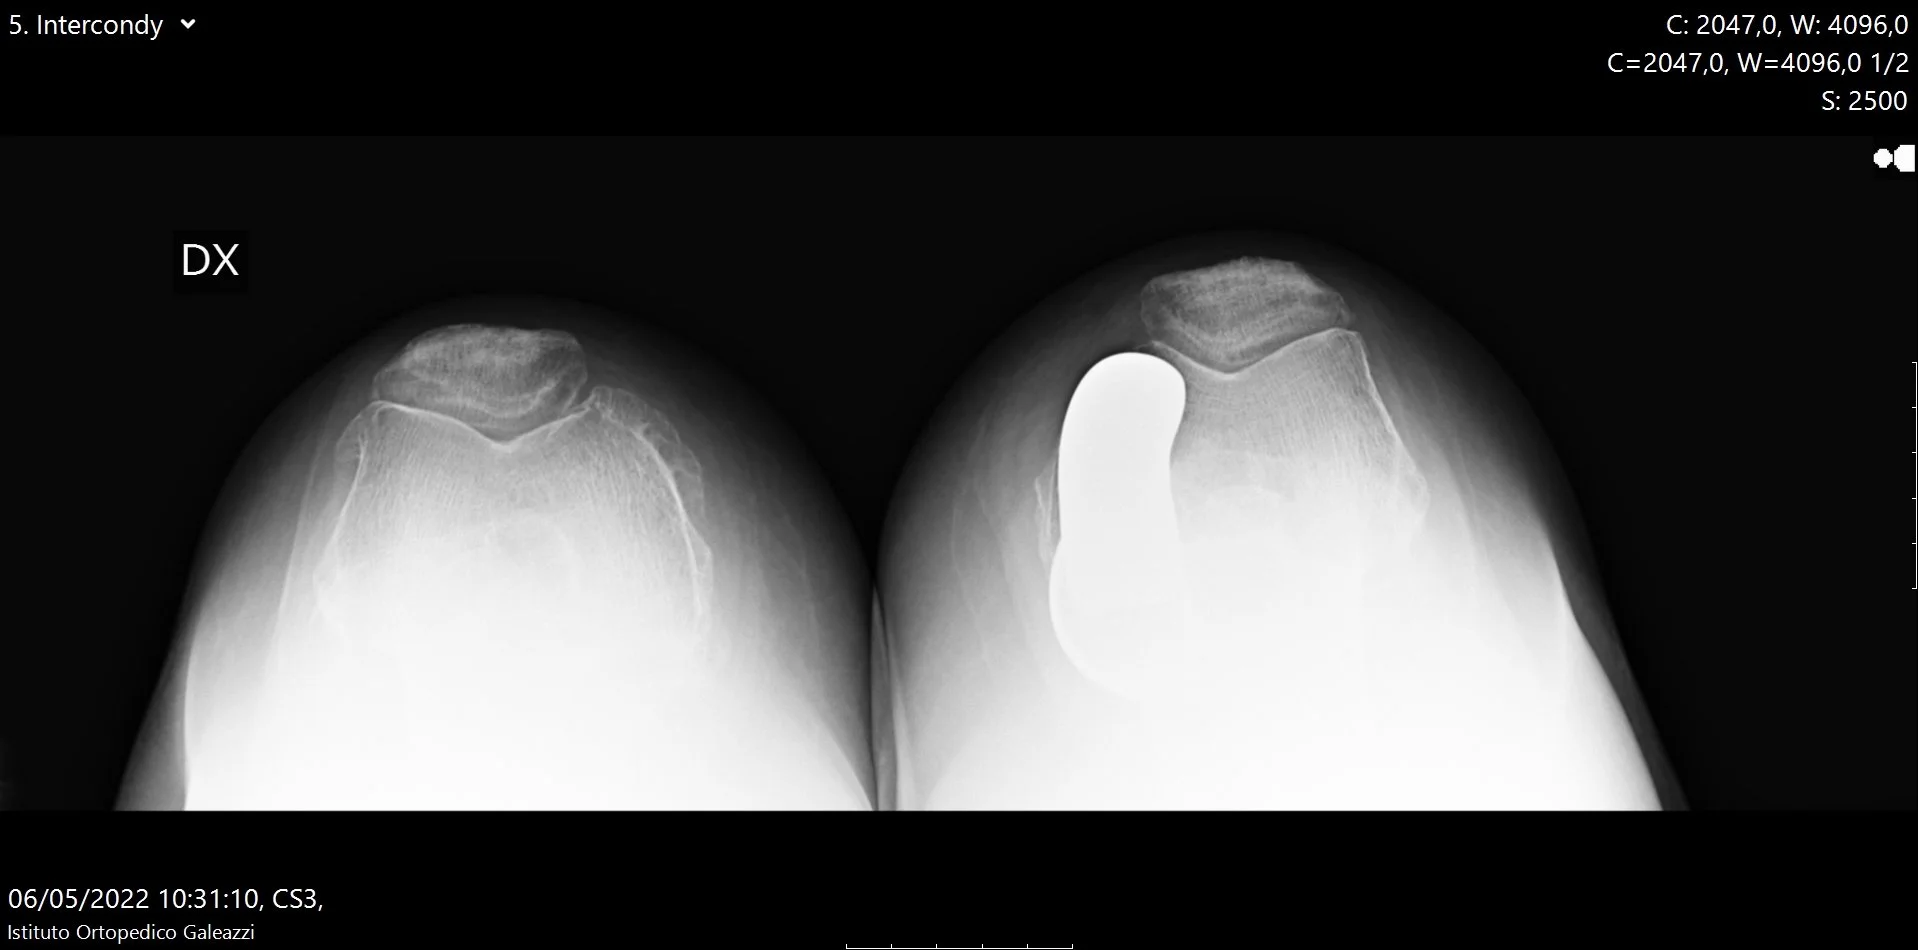

La radiografia assiale di rotula è una proiezione specifica che consente di osservare la rotula “dall’alto verso il basso”, mettendo in evidenza come essa scorre all’interno della troclea femorale durante la flessione del ginocchio.

Cosa consente di valutare

Questa proiezione permette di analizzare in modo accurato:

• l’allineamento della rotula, verificando se è centrata o deviata

• il rapporto tra rotula e femore, fondamentale per la distribuzione corretta dei carichi

• la presenza di segni di degenerazione cartilaginea femoro-rotulea

• eventuali alterazioni morfologiche che possono favorire attrito e sovraccarico

In presenza di artrosi femoro-rotulea, la radiografia assiale può mostrare una riduzione dello spazio articolare, irregolarità delle superfici o segni di sofferenza ossea che non sono visibili nelle proiezioni standard.

Radiografia assiale di rotula per valutazione dell’articolazione femoro-rotulea